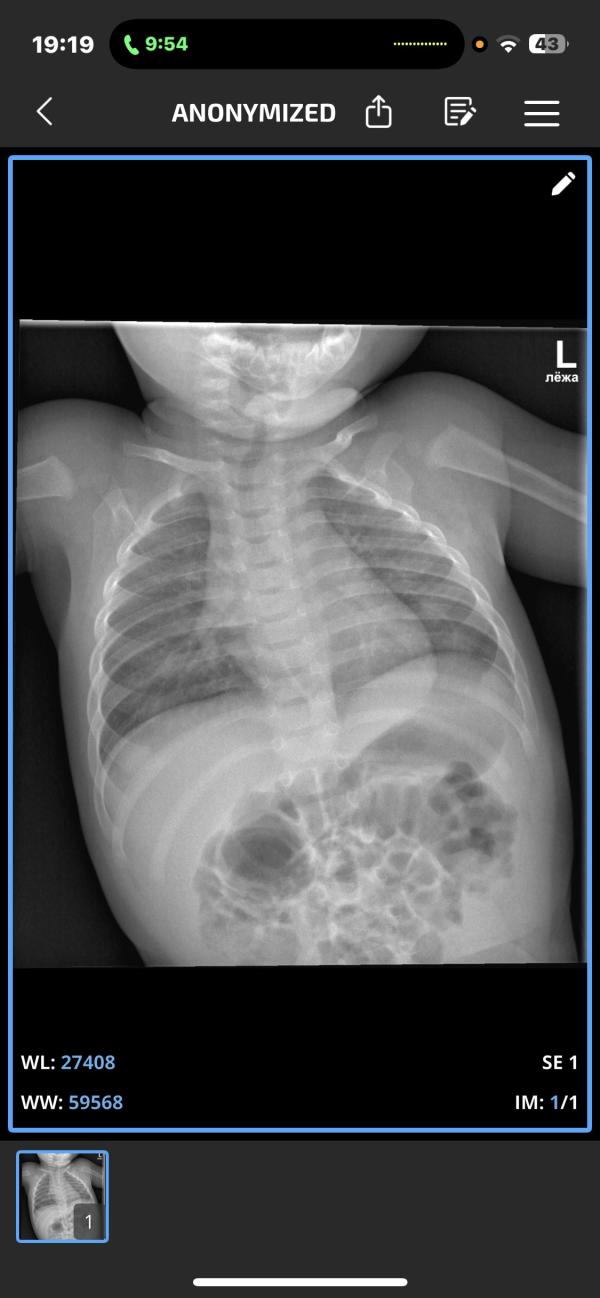

Девочки кто понимает в этих рентгенах сколько там поражено ?? До завтра с ума сойду(( щас сказали у малыша двусторонняя пневмония 😢